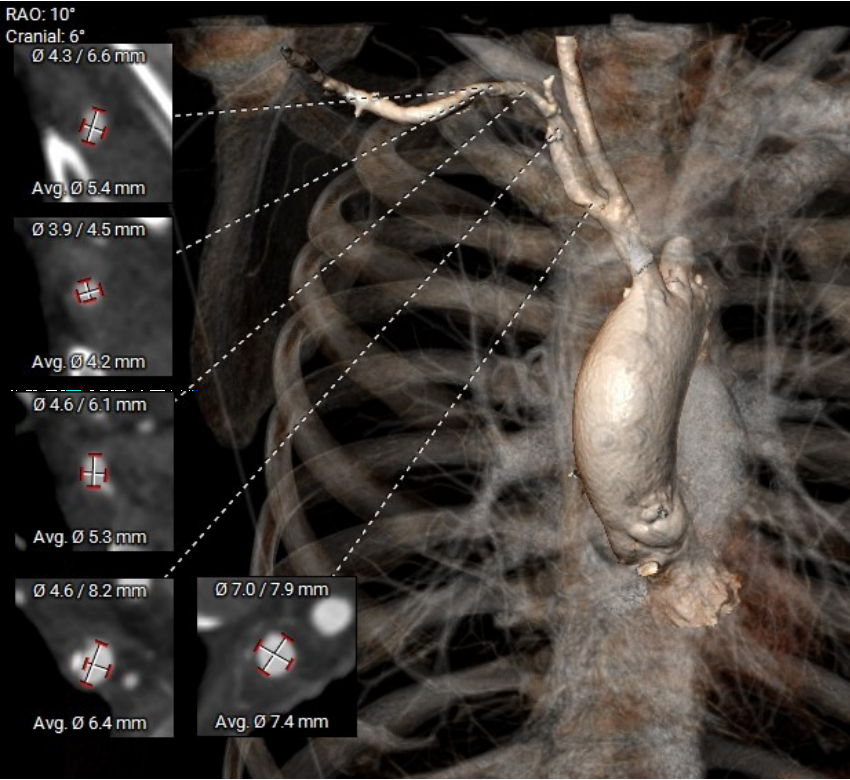

术前CT评估

根部结构:Type1二叶瓣(L-R型),左右之间纤维钙化融合嵴,轻中度钙化伴瓣叶增厚,瓣环:22.0mm,左室流出道 :22.1mm,瓦氏窦:33.1mm,瓣上限制区(supra-8mm):21.5mm,极小心腔。

瓣环:22.0mm

LVOT:22.1mm

SOV:33.1mm(高:9.5mm)

瓣上限制区:21.5mm

STJ:30.9mm(高:23mm)

AAO:35.7mm